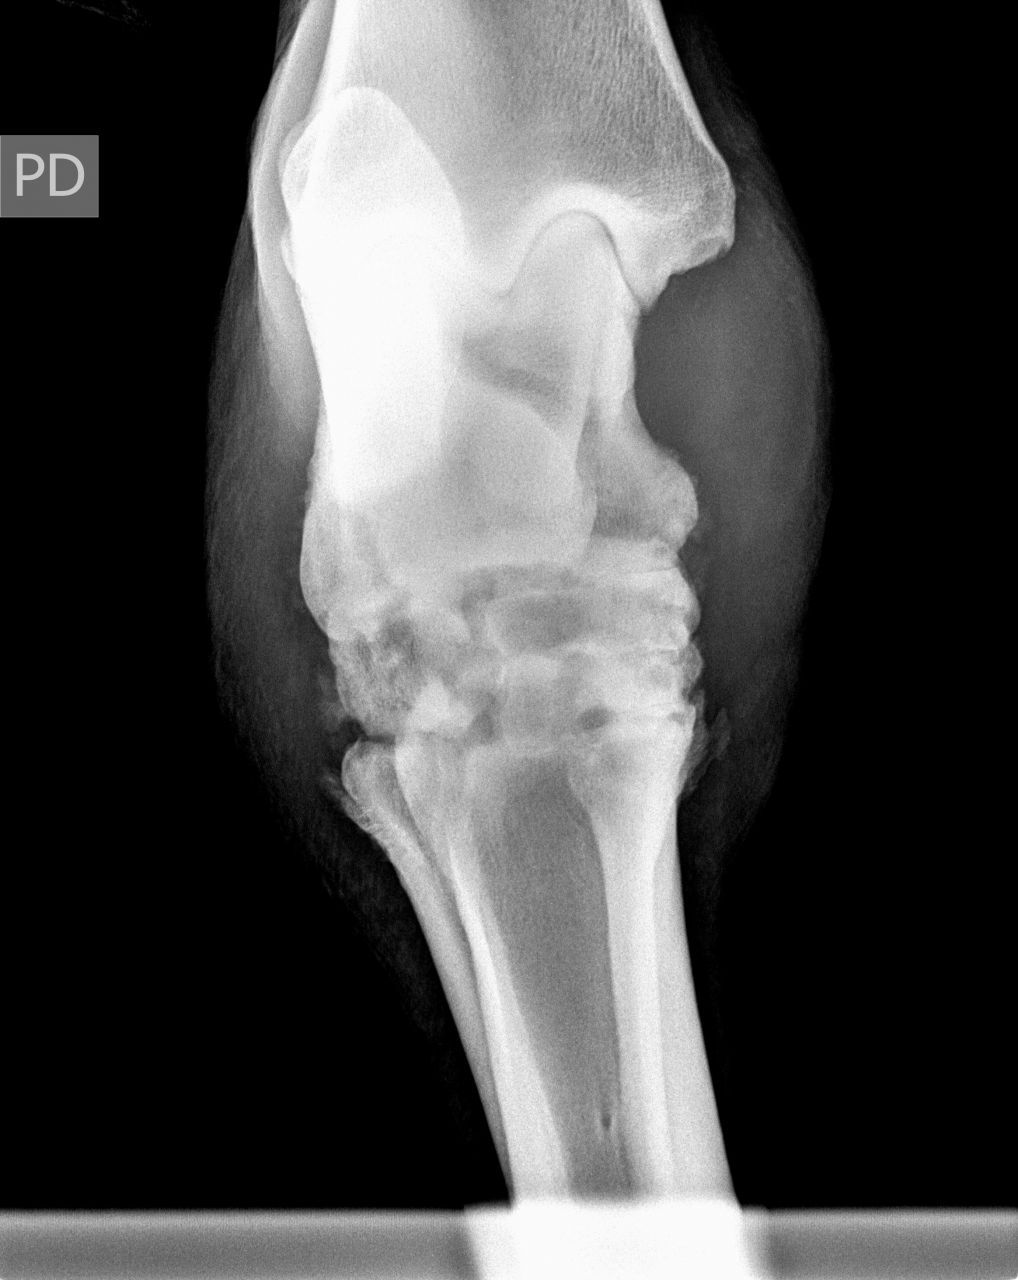

| Dire merci | Voici une radio prise en octobre 2010, [url=https://www.1cheval.com/membre/services/photos/images/191702.jpg" class='zoombox zgallery3279789' ] ![]() et une en décembre : [url=https://www.1cheval.com/membre/services/photos/images/191703.jpg" class='zoombox zgallery3279789' ] ![]() comme tu vois, c'était pas joli joli ! |

| Dire merci | Voici 2 autres clichés encore plus parlant : en octobre : [url=https://www.1cheval.com/membre/services/photos/images/191705.jpg" class='zoombox zgallery3279806' ] ![]() en décembre : [url=https://www.1cheval.com/membre/services/photos/images/191706.jpg" class='zoombox zgallery3279806' ] ![]() oh, tu sais, aujourd'hui, j'en parle s'en soucis et en étant contente du résultat, mais au moment où, je suis passé par des questionnements et des remises en cause pas possible, est ce que je fais bien, est ce que j'ai raison, ne devrais-je pas écouter les autres et ne pas m'acharner, etc...? sauf que les autres, ils ne sont pas à ta place, alors, j'ai écouté mon instinct. financièrement, j'y ai laissé des plumes, heureusement, les dépenses étaient étalées car dur avec un smic. Et pis, ben une fois qu'on a commencé, on va jusqu'au bout, pas possible à mi-parcourt d'arrêter, vaut mieux alors ne pas commencer. Je comprends par quoi tu passes. La fêlure de ton cheval n'est pas si grave que ca. Evidemment, c'est un mot impressionnant, surtout qu'on associe facilement chez le cheval fracture= fichu. Qu'est il envisagé comme soins pour ton cheval? Qui est-il? A quoi est-il destiné? |